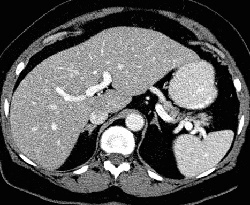

RADIOLOGY: ADRENAL: Case# 32926: ADRENAL NODULES. 72 year old female with right adrenal nodule identified on prior CT examination. Patient also has had a history of prior hysterectomy. A 1.2 cm low attenuation right adrenal lesion is again identified, unchanged in appearance. This lesion measured -18 Hounsfield units on noncontrasted CT examination and does demonstrate enhancement after contrast. A 2 x 1 cm left adrenal nodule is also identified. This lesion measures -8 to 7 Hounsfield units on noncontrasted CT examination and also demonstrates enhancement after contrast. Descending colonic and sigmoid diverticulosis is identified. There is no evidence of diverticulitis.